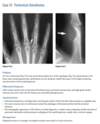

A lateral radiograph of the left foot demonstrates a prominent talar beak

­ (arrow) and bony sclerosis overlying the middle

facet (arrowheads). Coronal CT through the middle

facet shows talocalcaneal fusion, with bony bridging between the talus and the sustentaculum tali of the

calcaneus

Diagnosis: Tarsal coalition

Talocalcaneal coalition can result in dorsal beaking

of the talar head (Fig. 2.3.6, arrowhead), the so-called

C-sign (arrows)